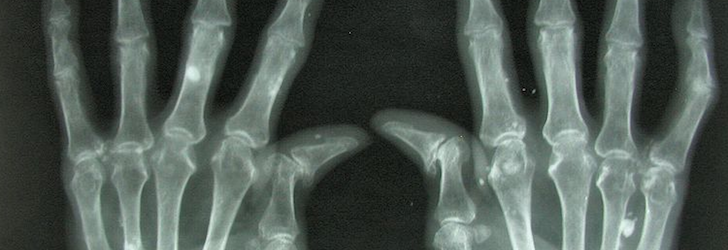

Survey: Rheumatoid Arthritis Patients Still Experience Pain Despite Treatment

Eight out of 10 people with rheumatoid arthritis (RA) reported experiencing pain every day or multiple times a week, according to the results of a new survey.1